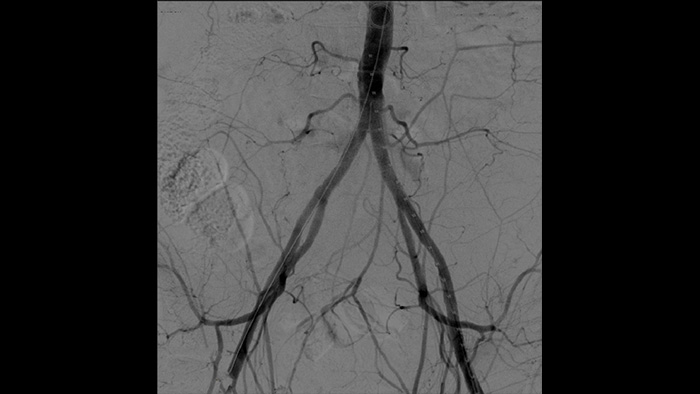

With the Philips Zenition mobile C-arm, Dr. Vila is obtaining outstanding high-quality images that allow him to perform most vascular procedures at the low dose setting.

With the Zenition, our DSA image quality has improved greatly. We no longer see a grainy image. We just see a very clear image."

Dr. R. Vila, MD

Bellvitge University Hospital, Barcelona, Spain

Digital subtraction angiography (DSA) is used in interventional vascular procedures to clearly visualise blood vessels by removing structures that can obscure vessel visibility. Roadmap fluoroscopy overlays a previously acquired subtracted contrast image on the live fluoroscopy, allowing you to track a device without reinjecting contrast.